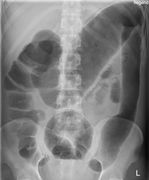

Gallstones (not sensitive)